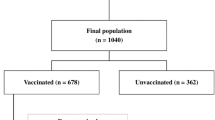

This study included 131 patients who were infected with the Delta variant of COVID-19. After screening, 106 patients with 458 follow-up CT scans were retrospectively selected and divided into complete and incomplete vaccination groups (66 and 40 patients, respectively). Imaging features were automatically extracted, and infection distribution in lung fields and progression pattern tendency were investigated. Furthermore, we extracted the most related clinical and imaging features to establish a vaccination status classification model. An independent testing dataset with 55 patients from another inpatient ward was enrolled to evaluate the generalizability of the model.